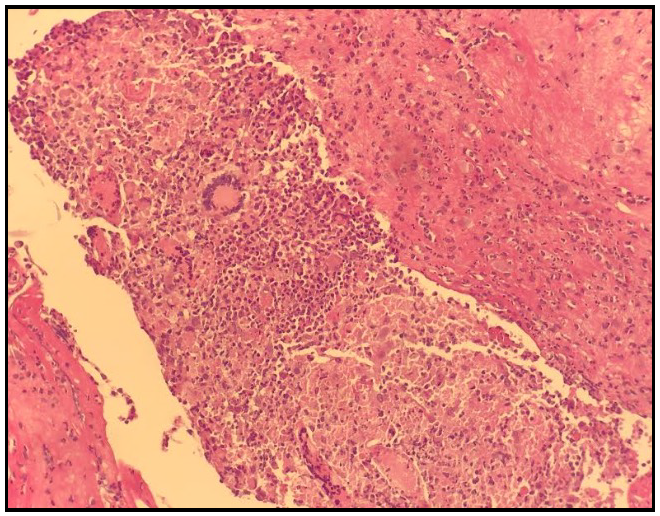

Faced with unfavorable evolution under empirical antibiotic therapy, we decided to withdraw the PD catheter on D+10, with biopsy of the peritoneum, the anatomic pathological examination of which showed a peritoneal coating altered by a granulomatous inflammatory infiltrate made up of epithelioid cells and giant cells with the presence of caseous necrosis (Figure 1 andFigure 2).

Figure 1.Biopsy of the peritoneum showing two granulomas with giant cells.

Figure 2.Biopsy of the peritoneum showing a giant cell granuloma with caseous necrosis.

If the indication for removal of the PD catheter has been retained, the typical appearance of the peritoneum is a scattering of disseminated or confluent granulations on a hyperemia peritoneal serosa or covered with a fibrinous exudate. Biopsy of the peritoneum is recommended, the characteristic histological appearance of which is epithelioid and giant cell granuloma with caseous necrosis in the center of the granuloma [18].